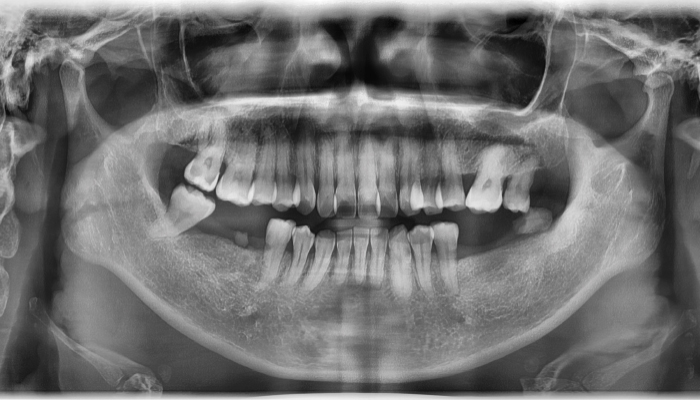

임플란트 시술을 위한 정밀진단

치아를 뺴고 오래 방치하거나 치아를 잡고 있는 치조골이 많이 녹은상태에서 치아를 빼면 위쪽 턱뼈가 부족할 수 있습니다.